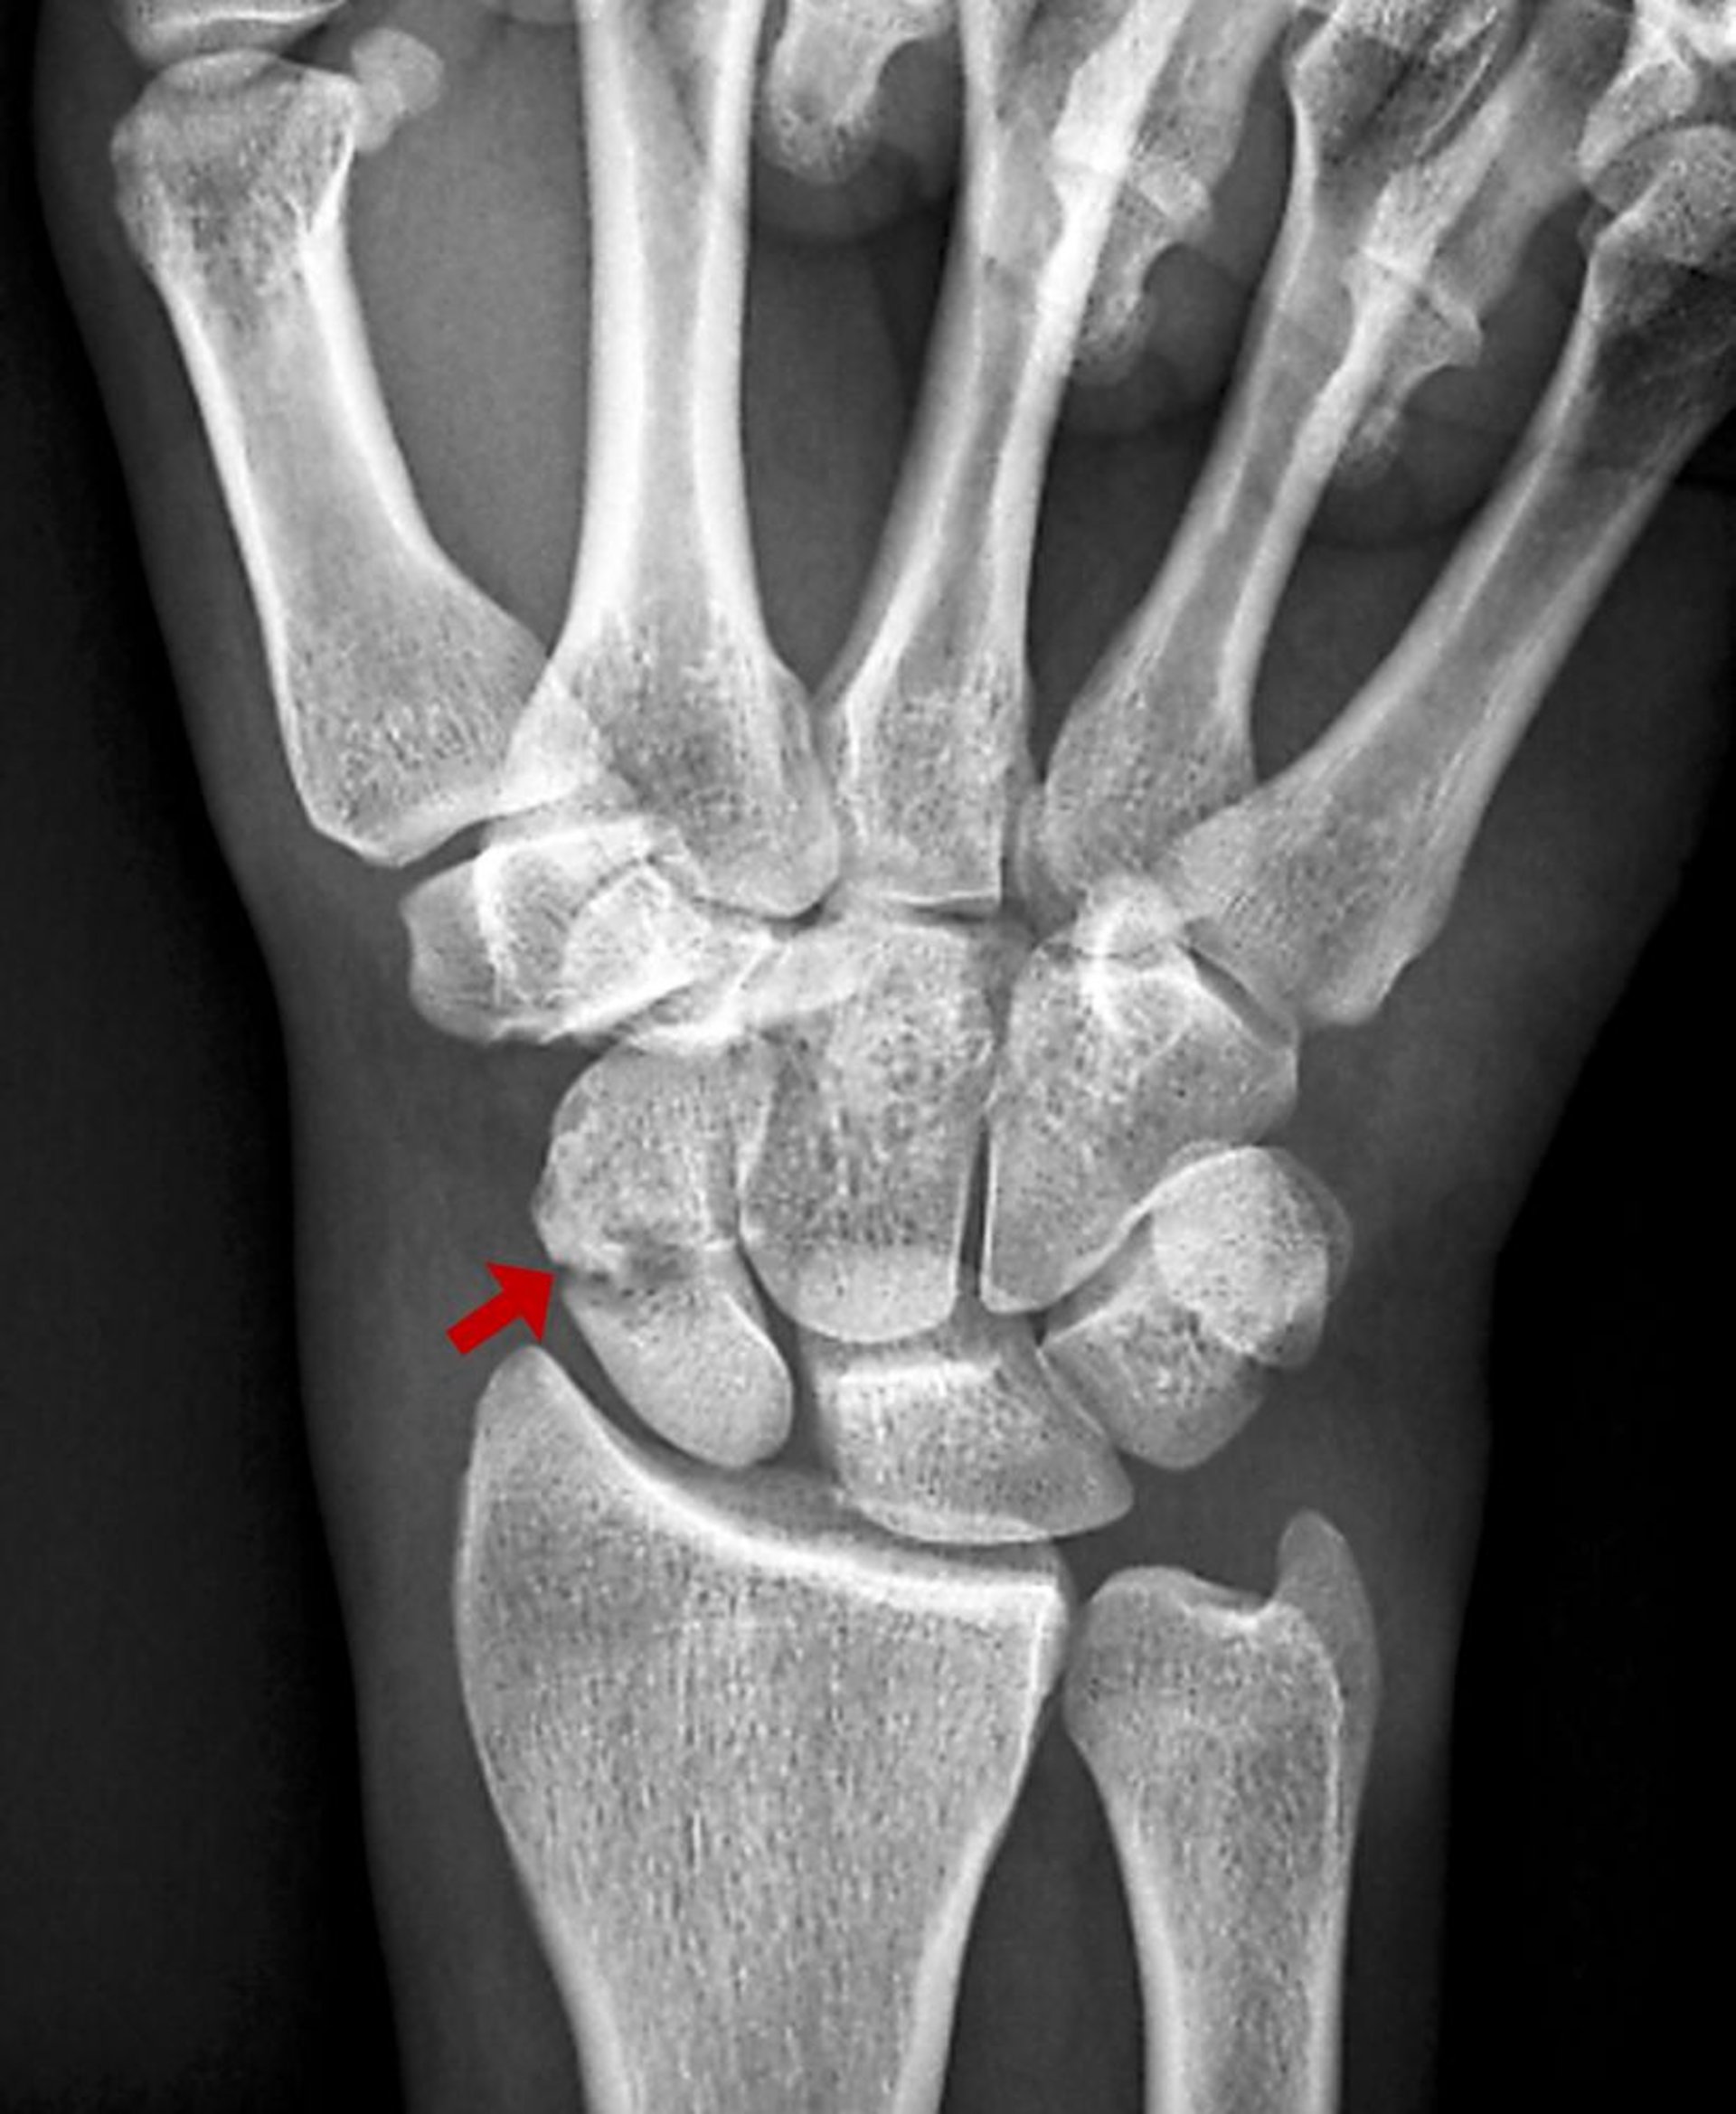

Frattura dello scafoide carpale

Questa frattura dello scafoide è visibile come una trasparenza all'RX.